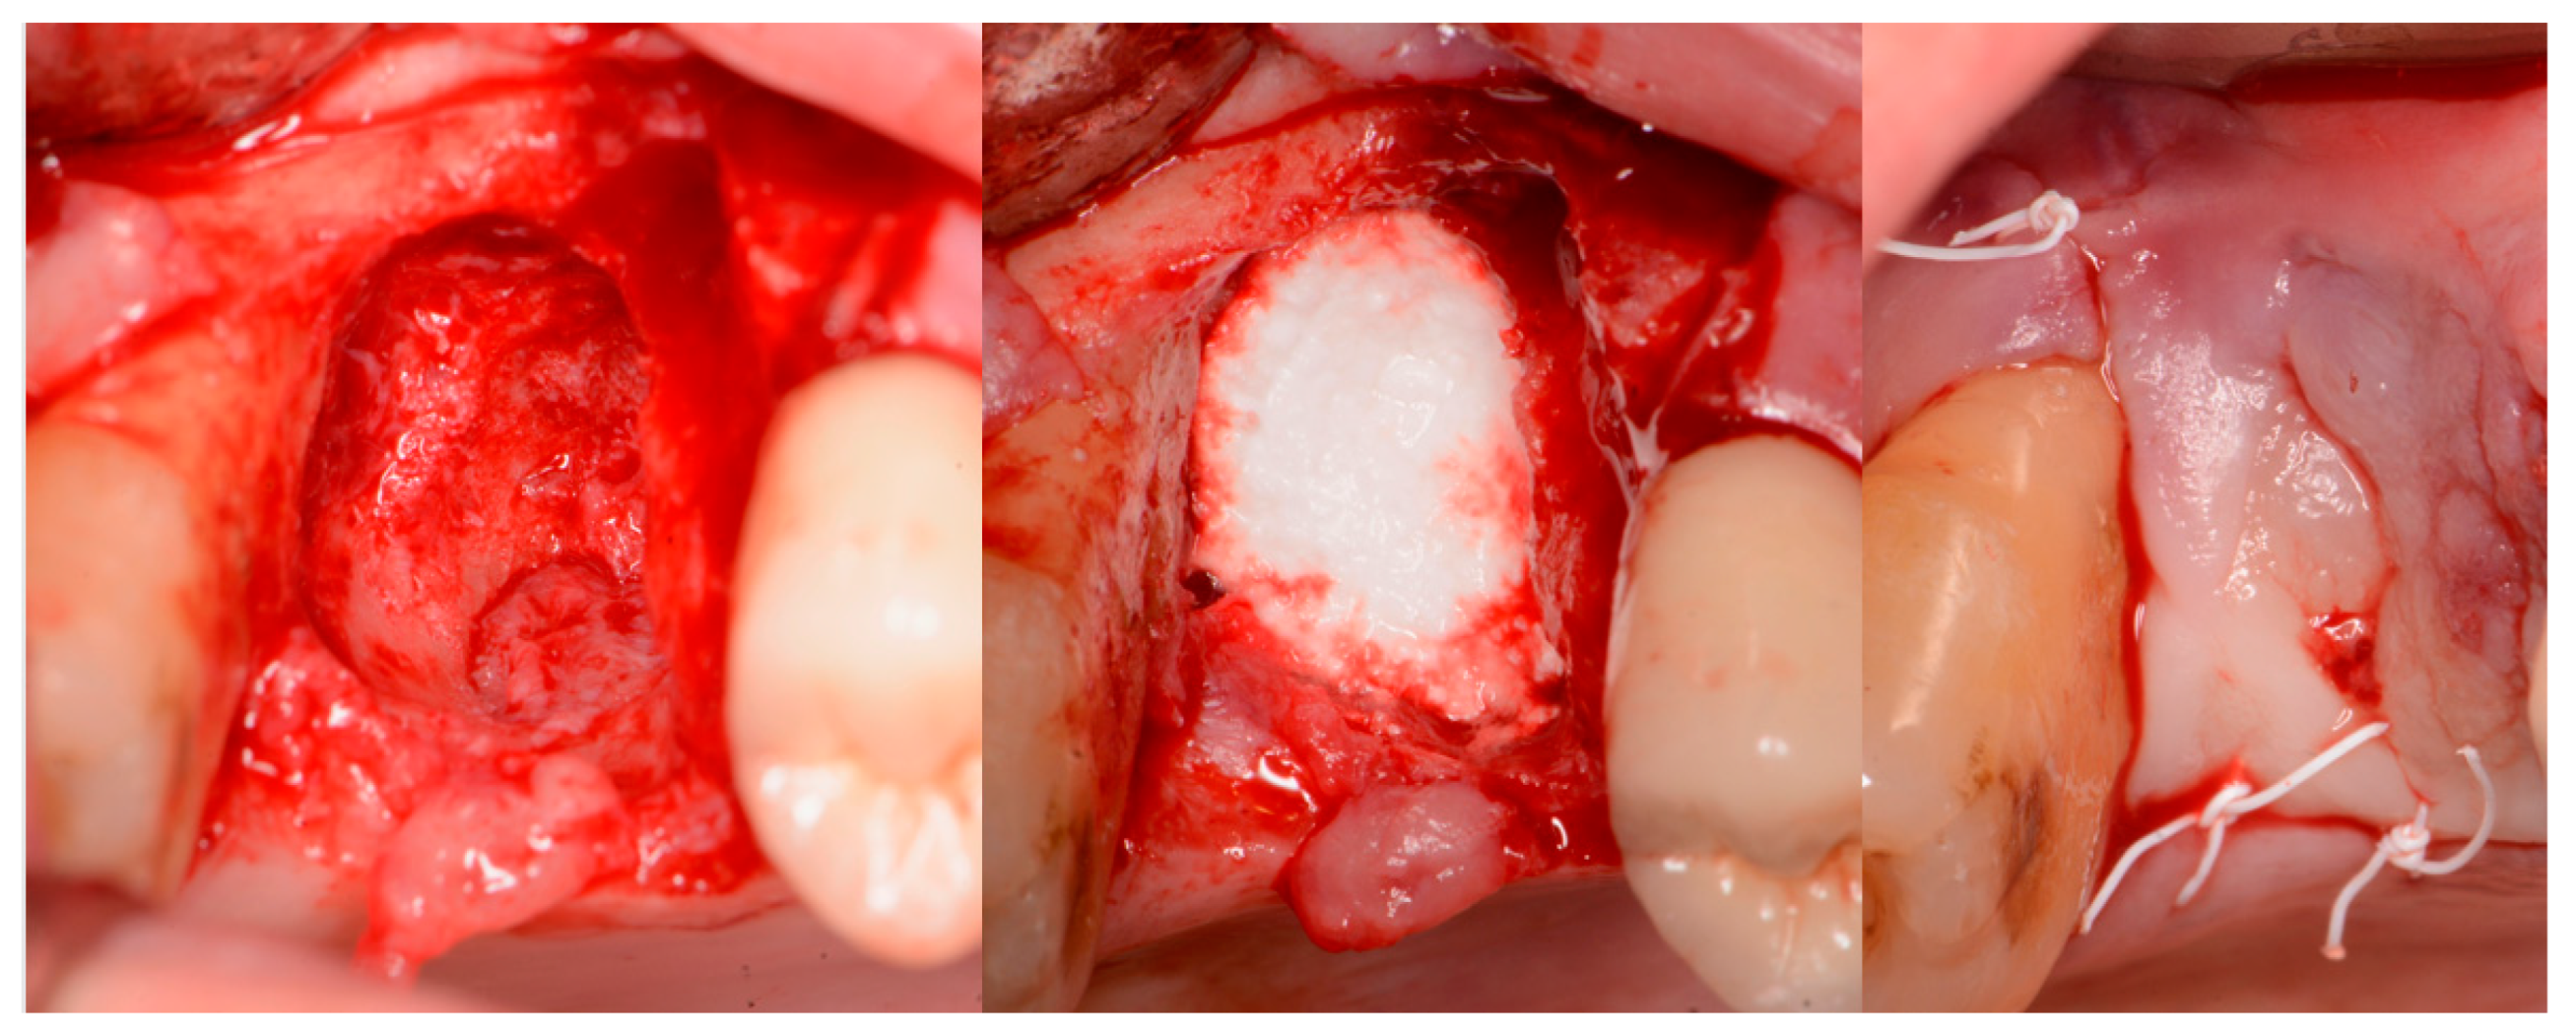

Local anesthetic was administered, and a full thickness flap of the area was elevated. Utilizing a similar technique as outlined in case 1, the 1st molar site underwent a crestal lift and a 4.5 × 8.5 mm Anyridge (Megagen, Busan, Republic of Korea) implant was placed (Figure 9). The defect present at the 2nd molar site, resulted in a crestal height of 1.5 mm, which was insufficient for implant stability if a simultaneous crestal sinus left was performed (Figure 9, middle). Thus, grafting would need to be performed to prepare the site for later implant placement. EthOss graft material was hydrated in the syringe as previously described and placed into the defect to increase crestal height following healing (Figure 9, right).

Figure 9.

Site was reentered at 10 weeks post-extraction and an implant was placed with a crestal sinus augmentation utilizing EthOss graft material at the 1st molar site and a large defect was present at the 2nd molar site (left), with a radiograph obtained to document the implant placement at the 1st molar and grafting of the defect (middle) and following crestal grafting of the 2nd molar site (right). Green line is the measurement of the height of the bone at that point between the crest and the sinus floor.